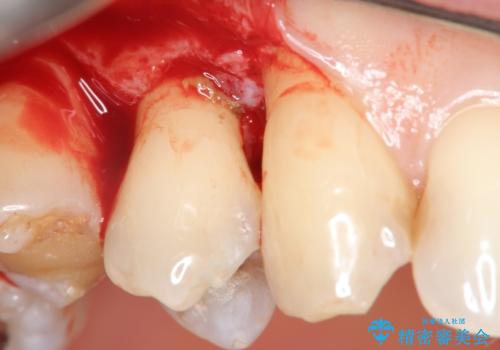

部分矯正を含む 歯周病治療 (再生治療・歯周ポケット除去・MTM・連結補綴)

検査の結果、強い歯ぎしりによる歯の周囲の骨の吸収が認められたため歯槽骨の再生・歯周ポケットの除去・力に対抗する連結補綴・補綴前処置としての小矯正を計画します。

今回連結補綴を行うにあたり、歯周病の問題を解決するために再生療法・歯周ポケット除去手術を、またより歯の神経を保存し力に対抗できる環境を整えるために小矯正を行い精度の高いメタルボンドクラウンを製作することができました。